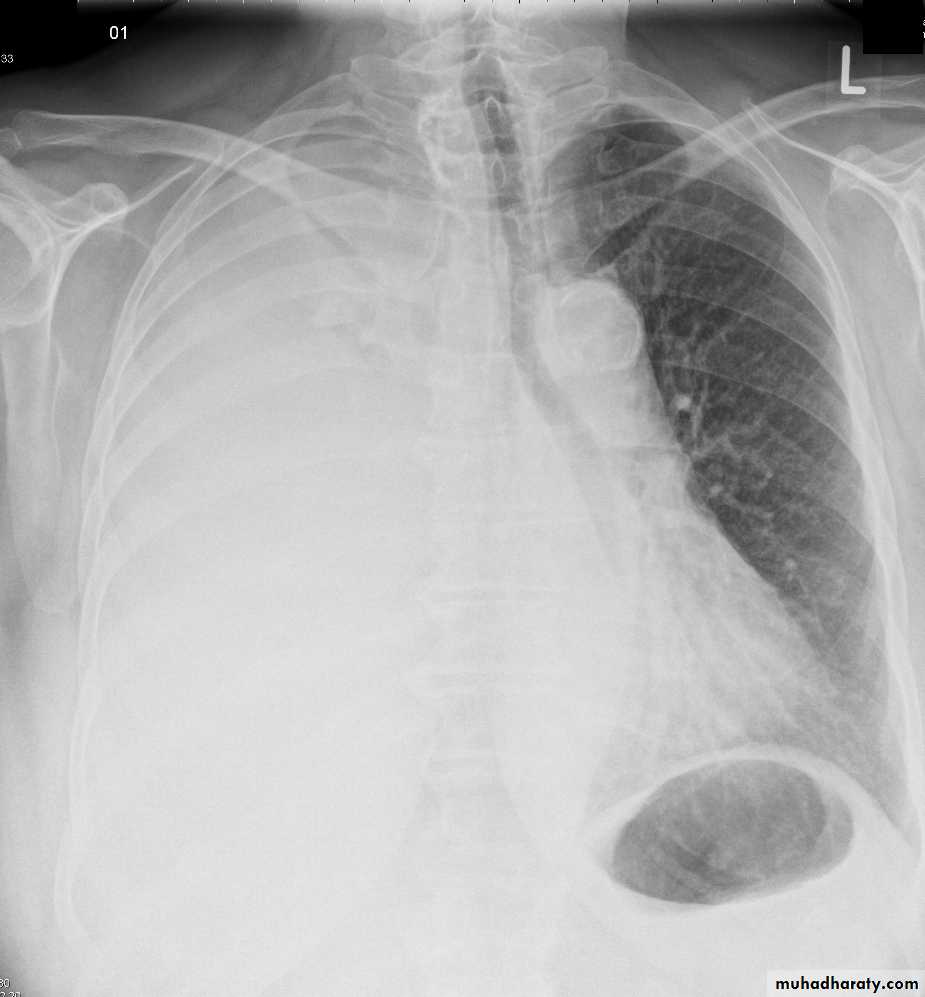

Pleural effusionPleural effusion tends to be used as a catch-all term denoting a collection of fluid within the pleural space. This can be further divided into exudates and transudates depending on the biochemical analysis of aspirated pleural fluid. Essentially it represents any pathological process which overwhelms the pleura's ability to reabsorb fluid.

Radiographic appearances

Plain radiographChest radiographs are the most commonly used examination to assess for presence of a pleural effusion, however it should be noted that on a routine erect chest x-ray as much as 250-600 ml of fluid is required before it becomes evident 6. A lateral decubitus film is most sensitive, able to identify even a small amount of fluid. At the other extreme, supine films can mask large quantities of fluid.

CXR (erect)

Both PA and AP erect films are insensitive to small amounts of fluid. Features include:

blunting of the costophrenic angle

blunting of the cardiophrenic angle

fluid within the horizontal or oblique fissures

eventually a meniscus will be seen, on frontal films seen laterally and gently sloping medially (note:

A subpulmonic effusion (infrapulmonary effusion) may be seen when there is previously established pulmonary disease, but can also be encountered in normal lungs , They are more common on the right, and usually unilateral

with large volume effusions, mediastinal shift occurs away from the effusion (note: if coexistent collapse dominates then mediastinal shift may occur towards the effusion)